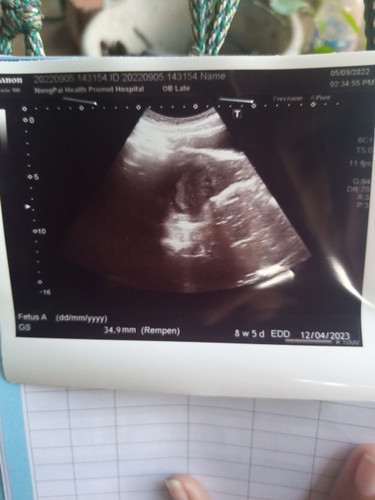

ท้องสองได้ 8w5d แล้วค่ะแต่ยังไม่เจอน้องเลย เจอแต่ถุงตั้งครรภ์ แม่ท่านไหนเคยเป็นบ้างค่ะ แม่กังวลมาก 😓😓

ตรวจผ่านหน้าท้องหรือช่องคลอดคะ ถ้าทางช่องคลอดจะเห็นเร็วกว่าค่ะ